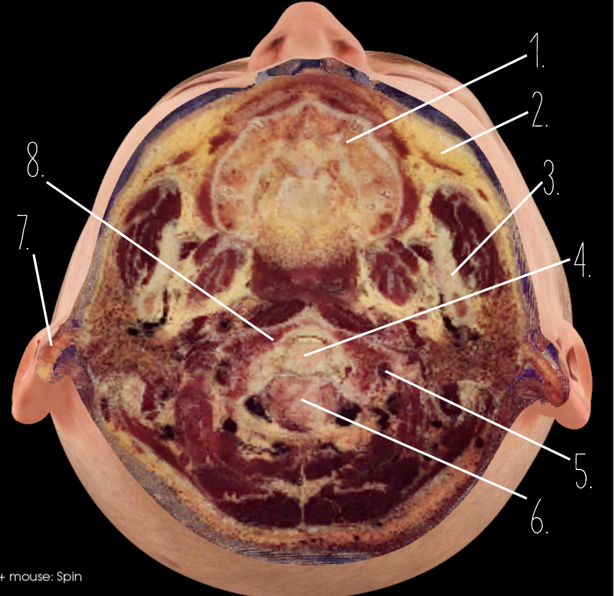

1?

Nasal Bone

2?

Maxillary Sinus

3?

External Acoustic Meatus

4?

Pons

5?

Cerebellum

6?

Mastoid Air Cells

7?

Mandibular Condyles

8?

Sphenoid Bone

9?

Maxillary Bone